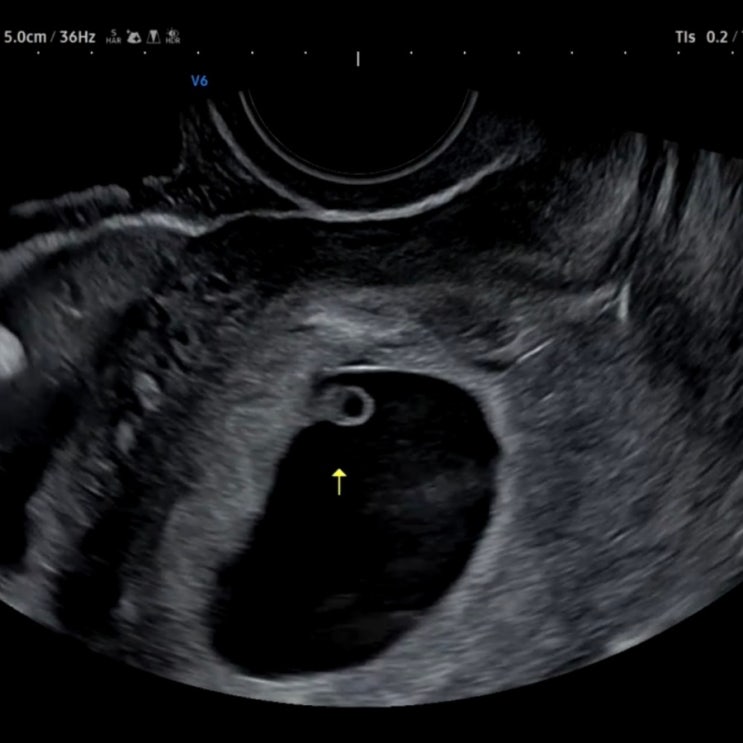

[임신 기록-2] 임신 6주차 / 초음파 아기집 확인 / 새집으로 이사

2024년 11월 25일 오전 산부인과로 돌진~~! 초음파를 보는데 너무 신기하고,, 안믿기고 반갑고 안뇽~~ 6주 ...